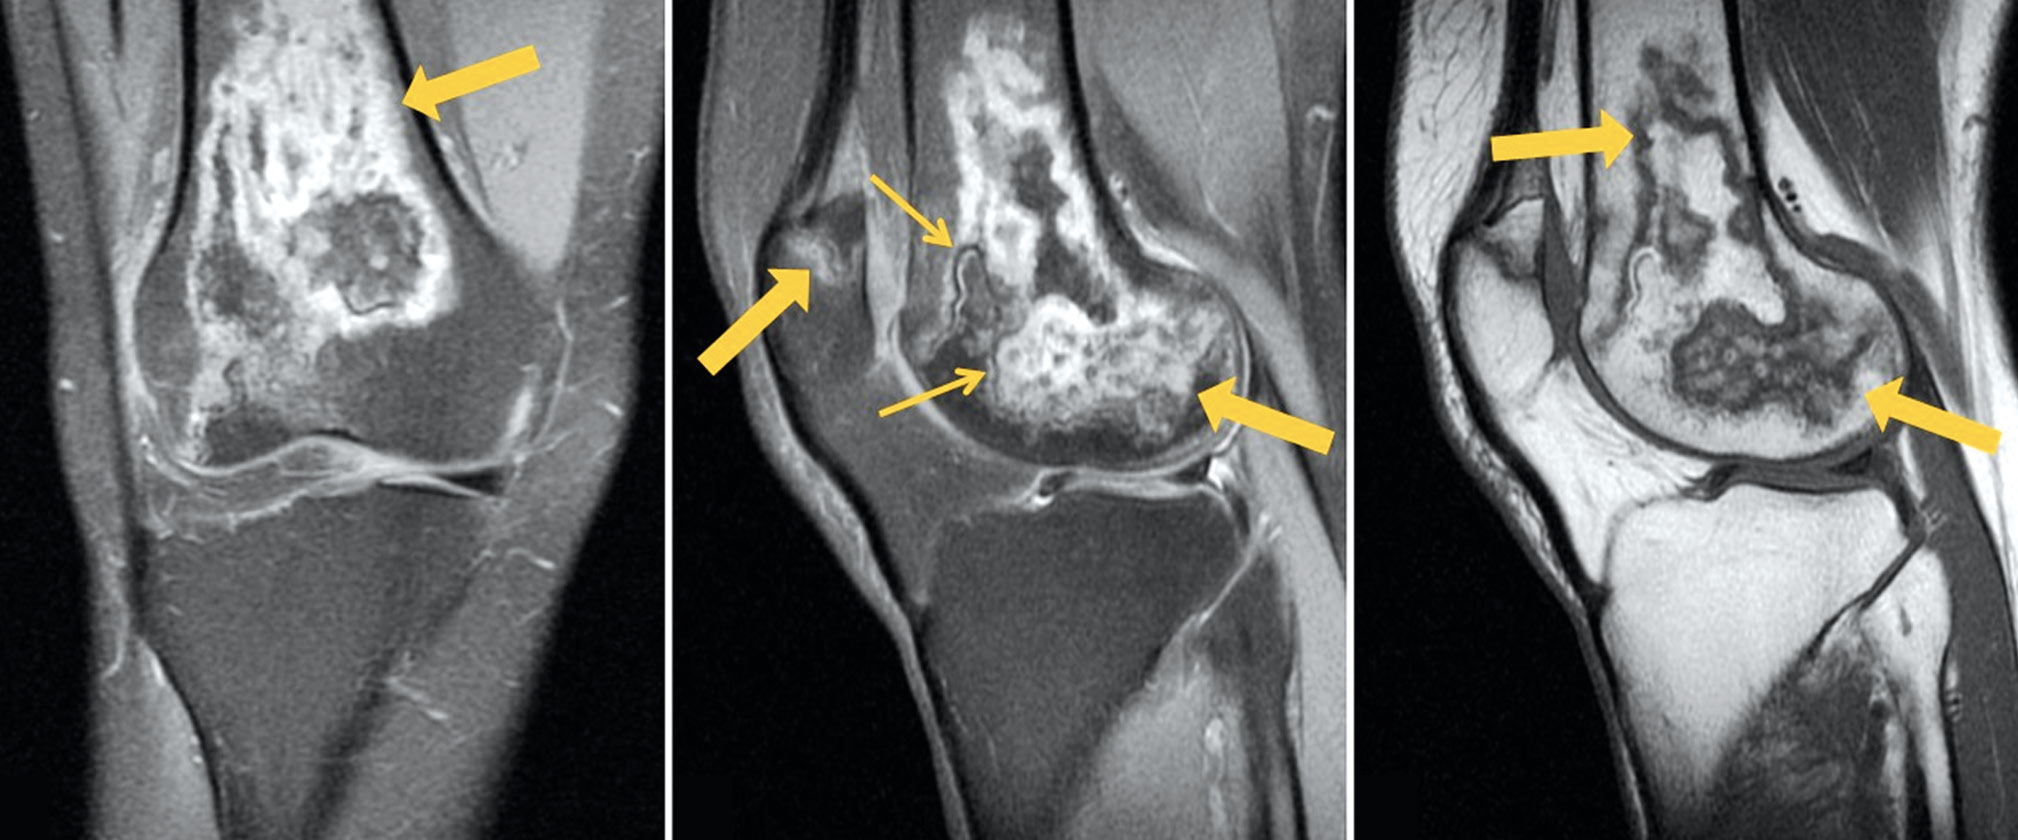

A follow-up MRI of both knee joints revealed positive changes: Previously identified lesions had become substantially less severe (Figs. 3 and 4).

Fig. 3. Follow-up MRI of the left knee joint: PDWI with fat suppression in the coronal (а) and sagittal (b) plane and T1WI in the sagittal plane (с). Thick arrows indicate areas of bone marrow edema in the form of a heterogeneous, irregularly shaped (“geographic”) MRI signal of femoral condyles and patella; the thin arrow indicates the “double line” sign in the form of internal hyperintense (granulation tissue) and external hypointense (osteosclerosis) lines on PDWI.